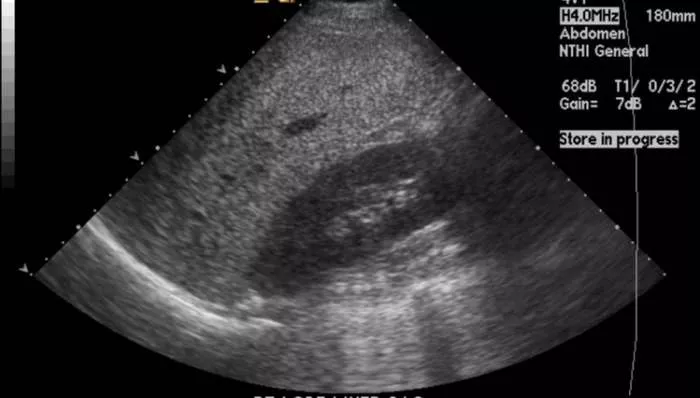

Ultrazvuk jetre

Masna jetra počinje sa uvećanjem jetre, koja je meka, zaobljenih ivica. Na ultrazvuku se vidi jetra koja je svetla, sija. Masna jetra se klasifikuje u tri stepena masnoće: normalna jetra, delimično masna jetra i masna jetra, kada su sve ćelije jetre ispunjene masnoćama, koje mogu biti u dve varijante. Nekada se kod masne jetre javlja bol pod desnim rebarnim lukom, nadimanje, mučnina ako se pojede hrana koja ne prija jetri i tegobe sa varenjem.